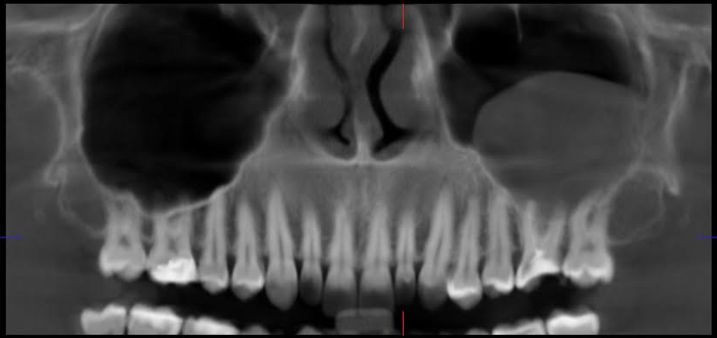

Surpriza a fost la radiografie, unde mi s-a descoperit un chist în sinusul drept, în maxilar. Chistul a pornit, cel mai probabil, de la o mică infecție la rădăcina acelei măsele și s-a umflat până la o dimensiune “medie”, ceea ce face intervenția de acum mult mai complicată. Nu-i ceva periculos, dar dacă mergeam acum doi ani la stomatolog, probabil că evitam totul.

Pata aia gri din dreapta imaginii este chistul.